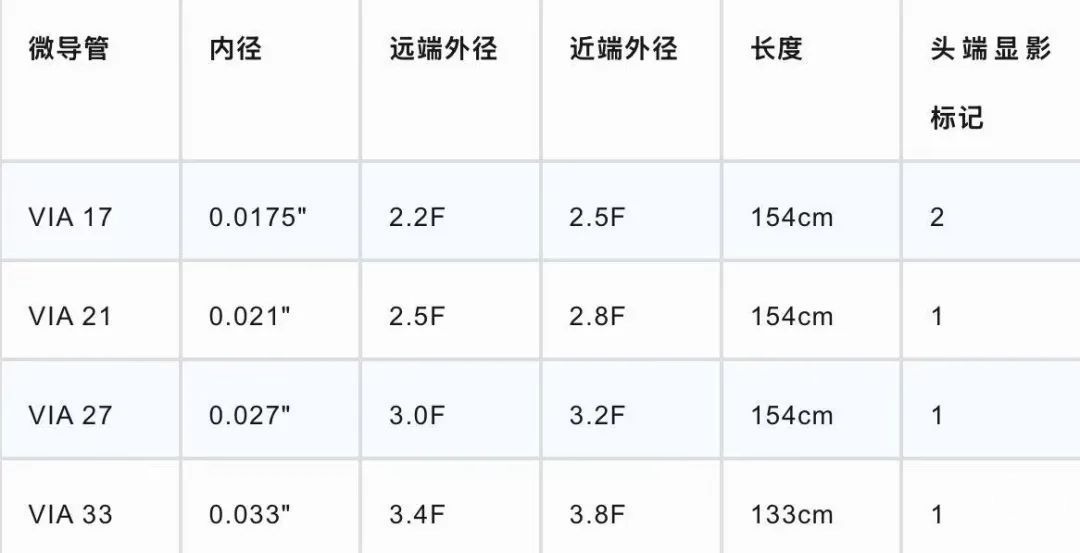

VIA™ 17微导管

病例二血管狭窄合并动脉瘤,血管纤细,WEB™植入避免了支架使用,相较于VIA™ 21,VIA™ 17更加纤细柔软,术中张力控制满意,导管更容易到位,到位后系统更稳定。WEB™ 17型号的新增、输送系统的优化,使其适用于更多复杂动脉瘤,为手术提供了充分的方案选择的空间,也更大程度的保证了手术安全。合并有左侧大脑前多发动脉瘤,可以二期密网支架植入治疗。

型号选择表